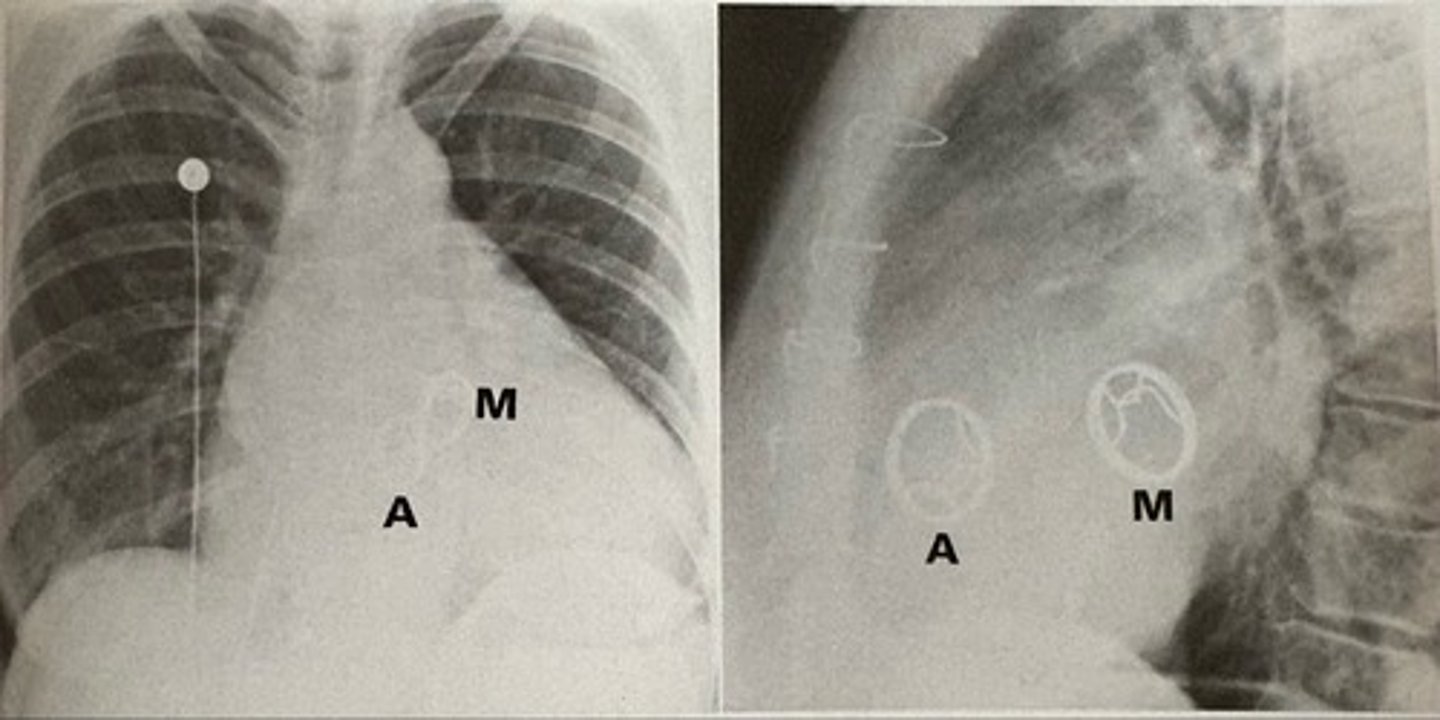

prosthetic aortic and mitral valves

what pathology is present?